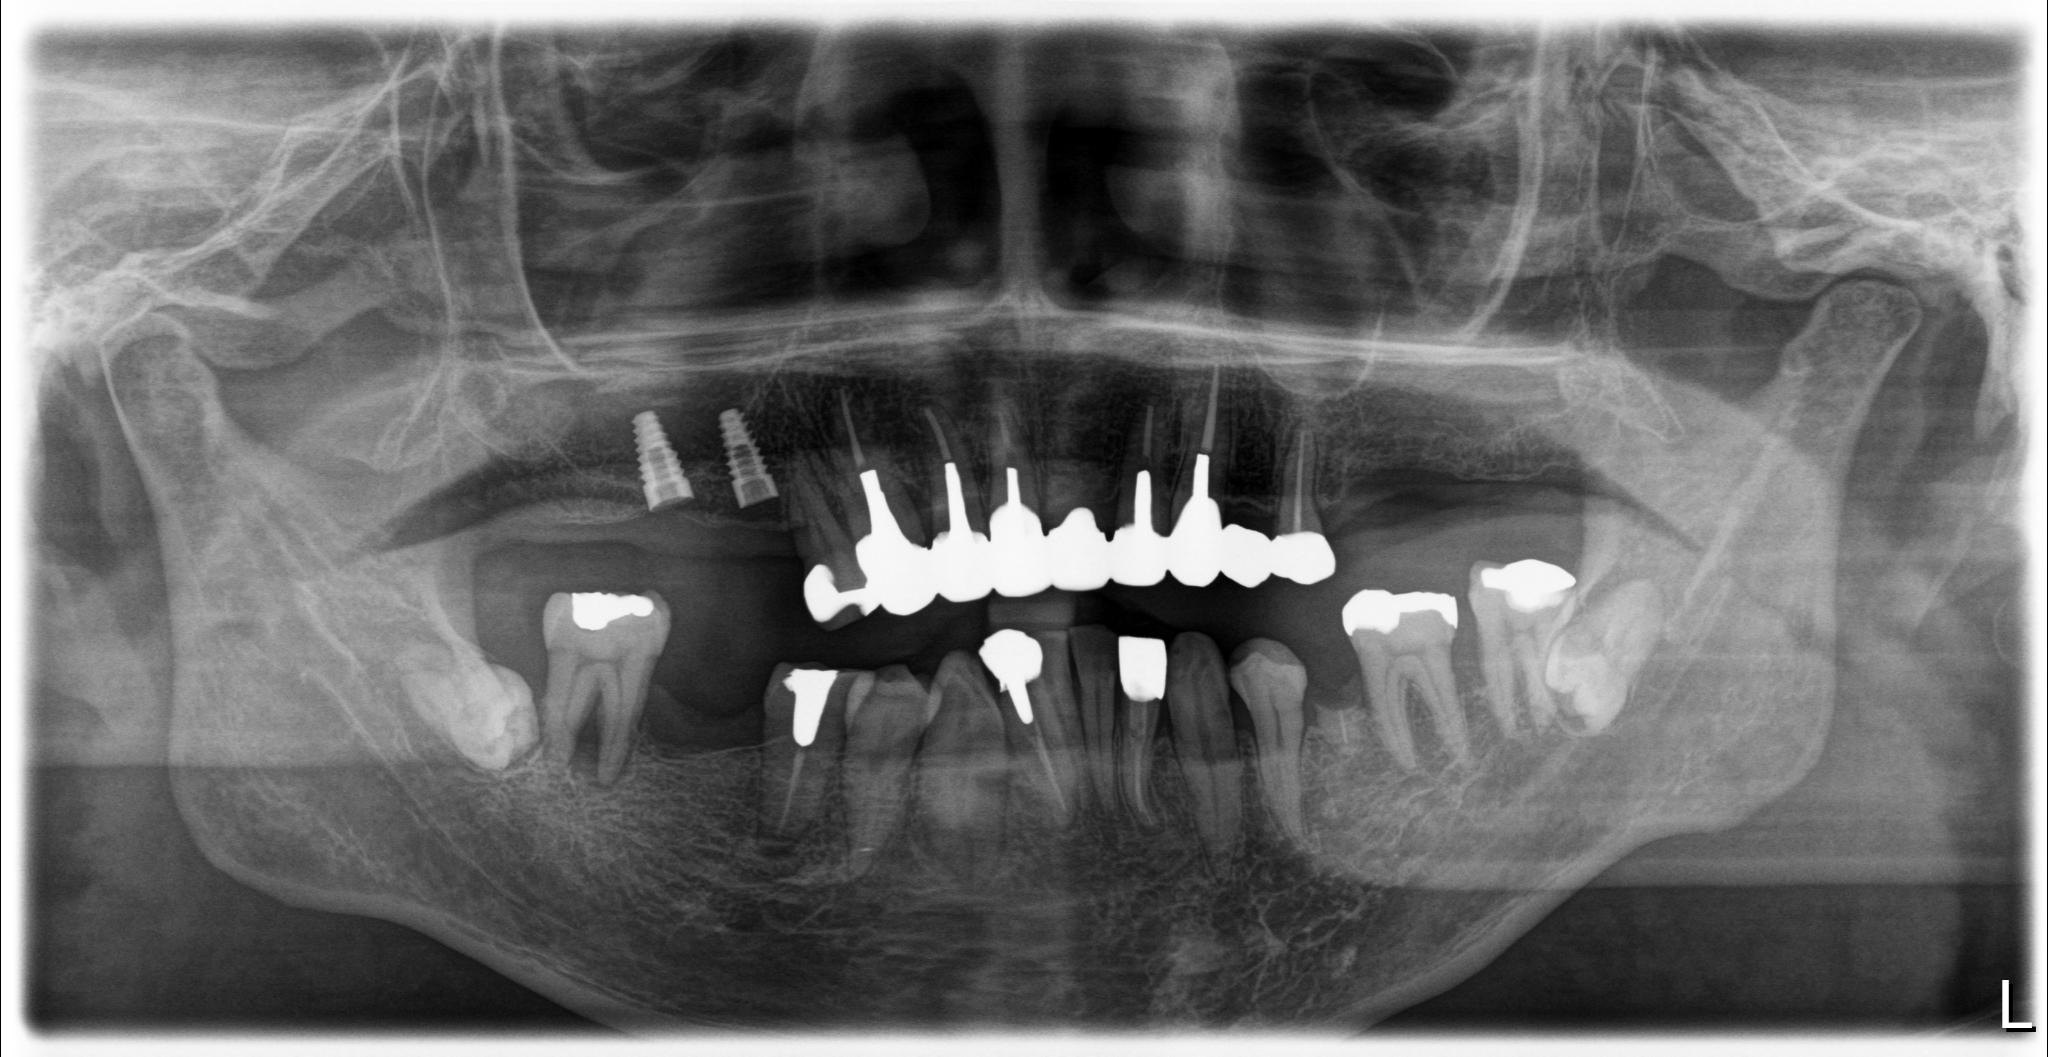

福岡県 49歳(男性)

「長年の口元の不安が負担」

術前

他院でインプラント治療を行っていましたが突然閉院となり、治療が中断されてしまいました。噛み合わせや歯並びに深刻な悩みを抱えることになり、口元の不安が負担になっていました。

相談の中でわずか1日で固定式の歯が入るスピード感に大きな魅力を感じました。

「ここなら長年の悩みが無くなるかもしれない」と感じ、手術を受ける決断をしました。

手術当日に歯が入り、その即時性に深く満足しています。これまでは人前で笑えないことが最大の悩みでしたが、これからは笑顔が増えていきそうです。